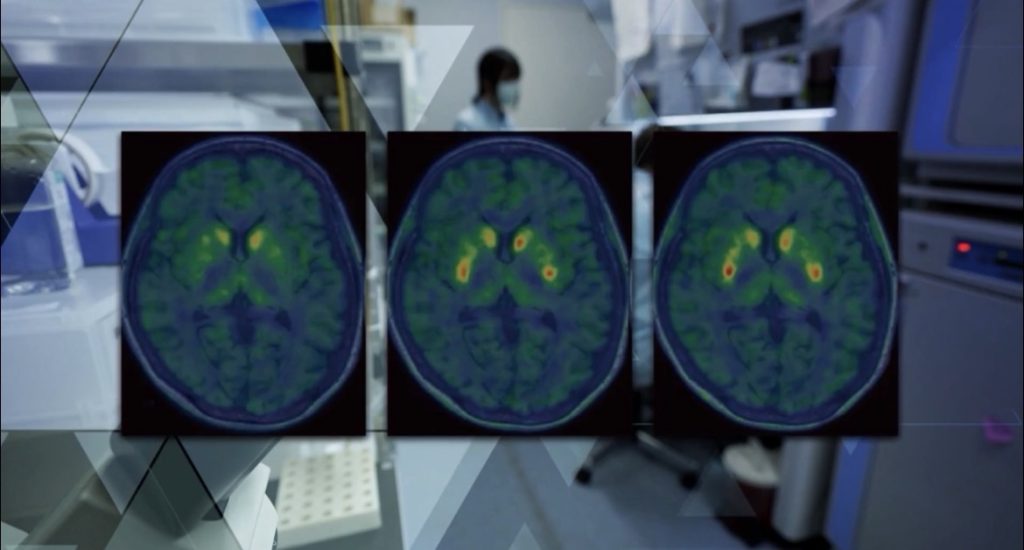

3. Transplante de Precisão: Utilizando cirurgia robótica e mapeamento por imagem, os novos neurônios são injetados no estriado, a área do cérebro responsável por coordenar os movimentos.